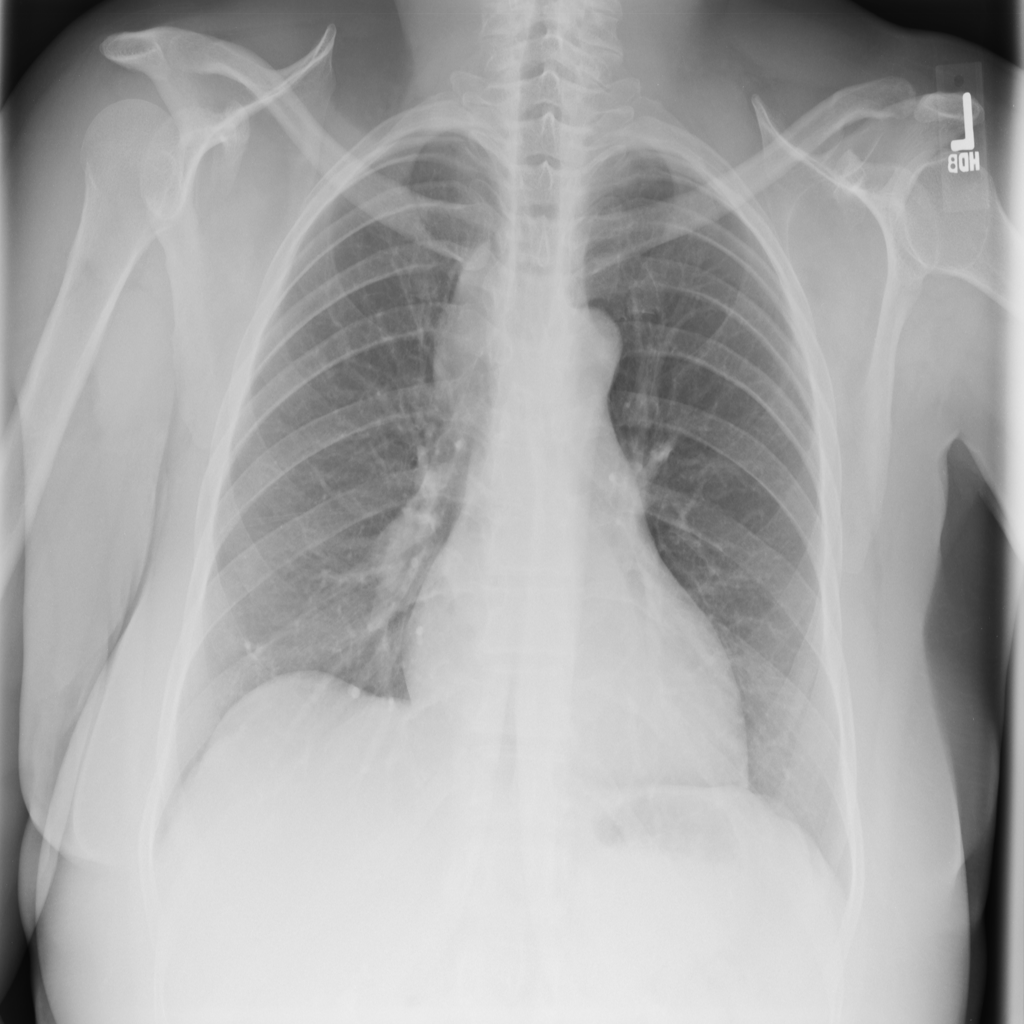

PAT-4639 · IMG-045Cardiomegaly

PAT-4639 · IMG-045

PA